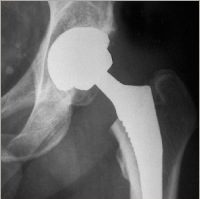

Radiographie simple

L’image radiologique est obtenue par atténuation d’un faisceau de rayons X qui traverse les différents tissus. Cette atténuation dépend de l’épaisseur de tissus traversés et également de la composition du tissu : plus l’épaisseur est importante, moins les rayons traversent et plus l’image est blanche ; plus les tissus contiennent des atomes de numéros atomiques importants, moins les rayons traversent et plus l’image est blanche. Ainsi l’os qui est une structure très dense est blanc et l’air des poumons est noir. Dans la pathologie de l’appareil locomoteur, la radiographie simple sert essentiellement à étudier la structure osseuse et la morphologie générale de l’articulation.